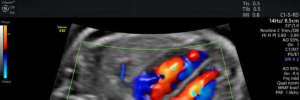

- Doppler obstétrico: como esse ultrassom ajuda a identificar complicações na gravidez

- A Importância do Ultrassom com Doppler na Saúde da Mulher e do Bebê